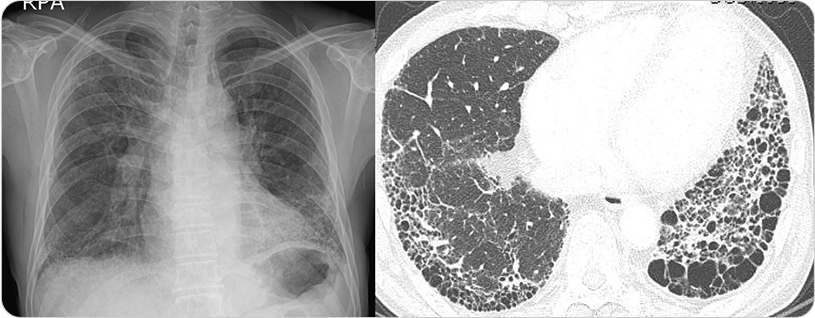

그림 : 간질성 폐질환 중 폐섬유화증을 보이는 흉부X선과 흉부전산화단층촬영(CT) 결과

폐의 폐포를 둘러싸고 있는 폐포의 벽에는 폐포상피세포, 내피세포, 혈관, 림프관, 기저막 등 다양한 조직이 있는데, 이를 간질(Interstitium)이라고 부르고,

이 공간에 질환이 초래된 경우를 통칭하여 ILD라 하며, 이 질환은 폐포벽, 모세혈관, 폐포 내 공간까지 침범합니다.

그래서 간질성폐질환(ILD)은 폐 간질부(interstitial compartment)의 증식과 함께 다양한 염증 세포들의 침윤, 그리고 때로는 섬유화(fibrosis)가 동반되는 질환을

통틀어서 말합니다. 간질성폐질환(ILD)의 진단을 위해서 흉부전산화단층촬영(CT) 후 임상소견, 그리고 폐 조직검사 등을 종합한 접근이 필요합니다.